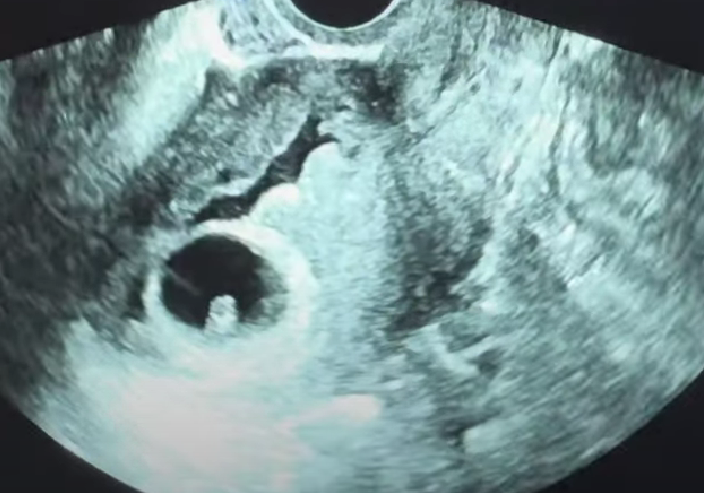

모든게 처음인데다 걱정인형이라 조금만 불안해도 병원행이다. ^^ 산부인과만 대체 이번주에 몇 번을 가는지...^^ 여튼 피가 아주 조금 비쳐서 초음파를 봤는데 출혈은 없다고 했다. 만성 염증에 시달리고 있는 자궁경부가 조금 헐었는지, 조금만 건드려도 피가 나온다고 해서 처치했다. 아마 거기서 나온 출혈인가 싶기도(?) 그리고 초음파도 혹시 몰라서 같이 봤는데 피고임이 있었다. 며칠 전만 해도 피고임 누구나 있을 정도라 신경 안써도 된다고 했는데..!!! 이번에는 피고임이 훨씬 더 많이 퍼져있었던 것 같다. 흑흑. ㅠㅠ 선생님이 유산 어쩌고 이런 얘기 해서 난 또 한가득 걱정을 이고 돌아왔으나 며칠 지나니 좀 괜찮아짐. 주사 맞고 그럴 정도는 아니었으니 괜찮을 거야~~~~~ 역시 초기에는 조심 또 조심!!!!

아래 초음파에서 애기집 위에 보이는 까만게 다 피다. ^^ 지금은 다 잘 흡수되었기를.